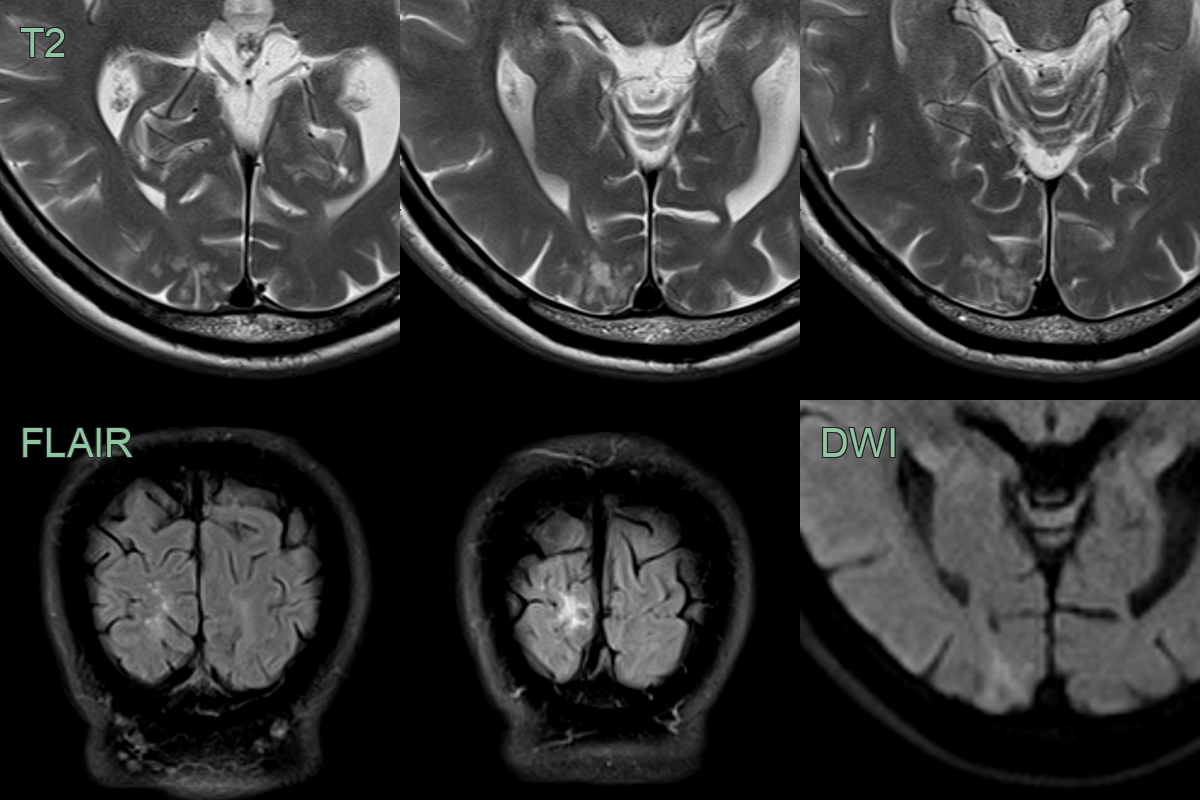

• Incidental T2-hyperintense lesion without mass effect in the right occipital lobe. There was neither diffusion restriction nor pathological enhancement.